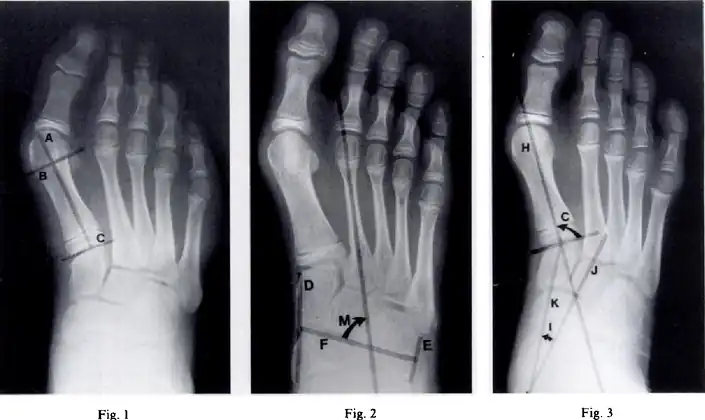

Metatarsus (primus) varus-Fig 1 - Length of the lateral cortex of the first metatarsal, Fig 2-metatarsus adductus angle measures the position of the lesser tarsus relative to the midfoot, Fig 3- the cuneiform angle

A Sgarlato's angle of more than 15° indicates pigeon toe.[9]

Pigeon toe can be diagnosed by physical examination alone.[10] This can classify the deformity into "flexible", when the foot can be straightened by hand, or otherwise "nonflexible".[10] Still, X-rays are often done in the case of nonflexible pigeon toe.[10] On X-ray, the severity of the condition can be measured with a "metatarsus adductus angle", which is the angle between the directions of the metatarsal bones, as compared to the lesser tarsus (the cuneiforms, the cuboid and the navicular bone).[11] Many variants of this measurement exist, but Sgarlato's angle has been found to at least have favorable correlation with other measurements.[12] Sgarlato's angle is defined as the angle between:[9][13]

- A line through the longitudinal axis of the second metatarsal bone.

- The longitudinal axis of the lesser tarsal bones. For this purpose, one line is drawn between the lateral limits of the fourth tarsometatarsal joint and the calcaneocuboid joint, and another line is drawn between the medial limits of the talonavicular joint and the 1st tarsometatarsal joint. The transverse axis is defined as going through the middle of those lines, and hence the longitudinal axis is perpendicular to this axis.

This angle is normally up to 15°, and an increased angle indicates pigeon toe.[9] Yet, it becomes more difficult to infer the locations of the joints in younger children due to incomplete ossification of the bones, especially when younger than 3–4 years.